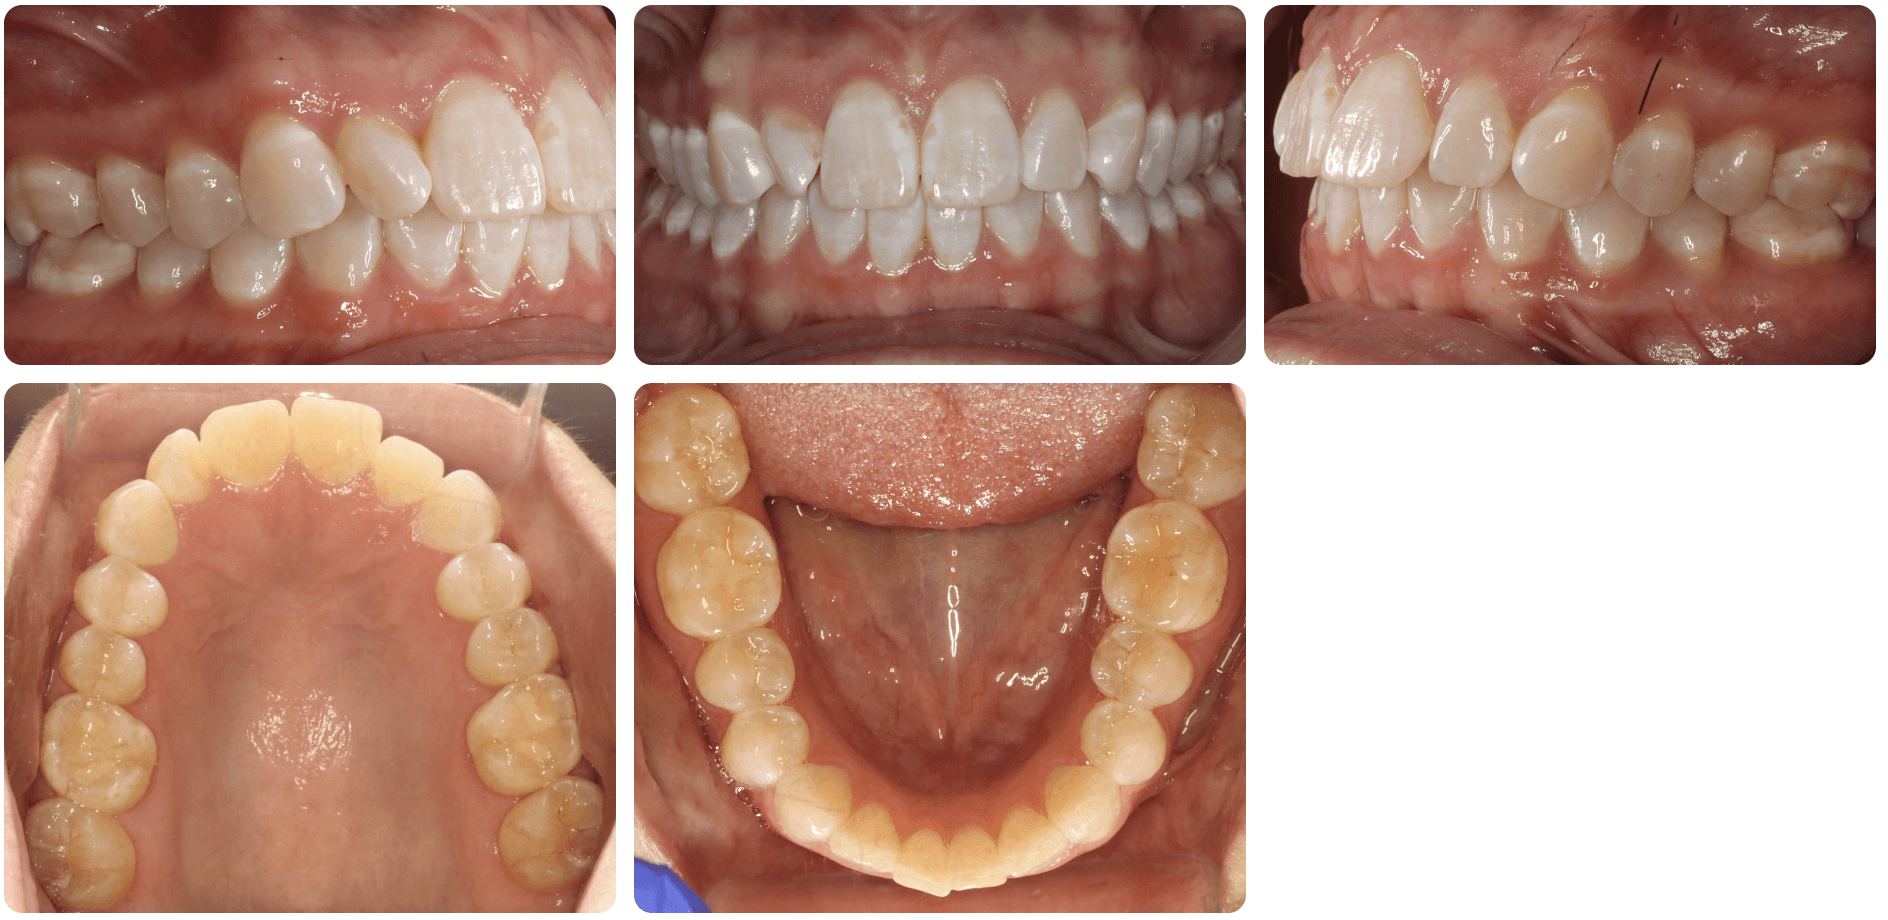

Diagnosis: Deep bite, lower anterior crowding, rotated upper lateral, arch misalignment, wear on teeth from grinding

Adjuncts: Attachments, IPR

Initial treatment

INTRAORAL